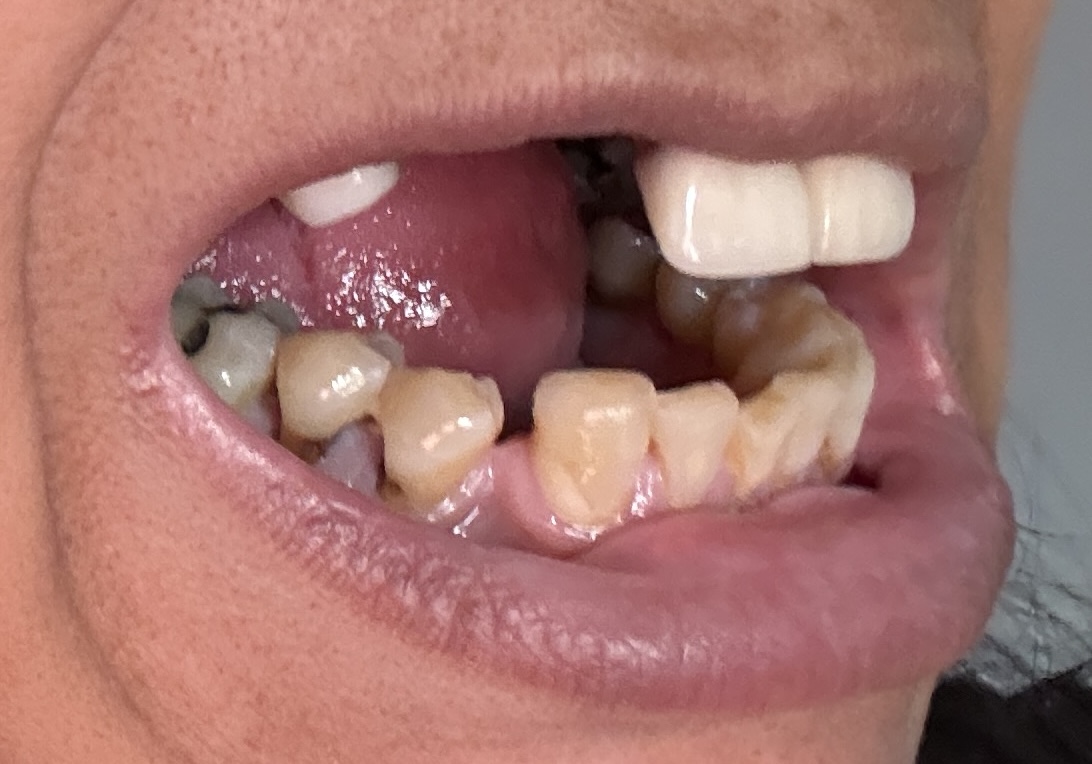

Dental Auction No. 11561: Several extractions and All-on-4 Top and bottom arches

12,13,14 have had root canals in past and now have quite a bit movement. 2-5 have all had root canals in past and now the crowns are breaking down.

Overall information (lower arch)

Overall, all of my gums have receded and most of the bottom teeth are exposed w/ some roots and there are many cavities.